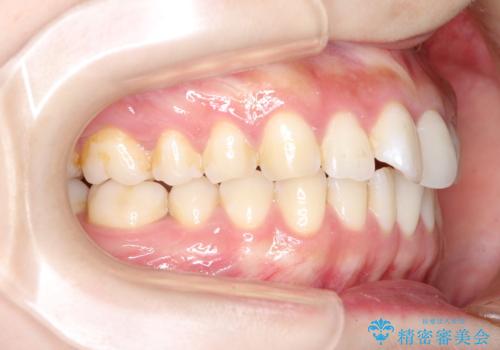

- 前歯の見た目の改善を希望され来院された患者様です。

初診時の歯並びの状態としては、上下にガタガタがある状態であり、特に上の前歯(左上1番)の捻じれを最も気にしていらっしゃいました。

口元の位置も悪くなくスペース必要量も軽度であったため、非抜歯/マウスピース矯正にて治療を行いました。

前歯の捻じれを改善するためにスペースを作る必要があり、前歯の歯の間を削って簡単に直す方法もありますが、奥歯のズレが認められたため、大臼歯後方のスペースを利用し、根本的な原因からしっかりと治療を行いました。